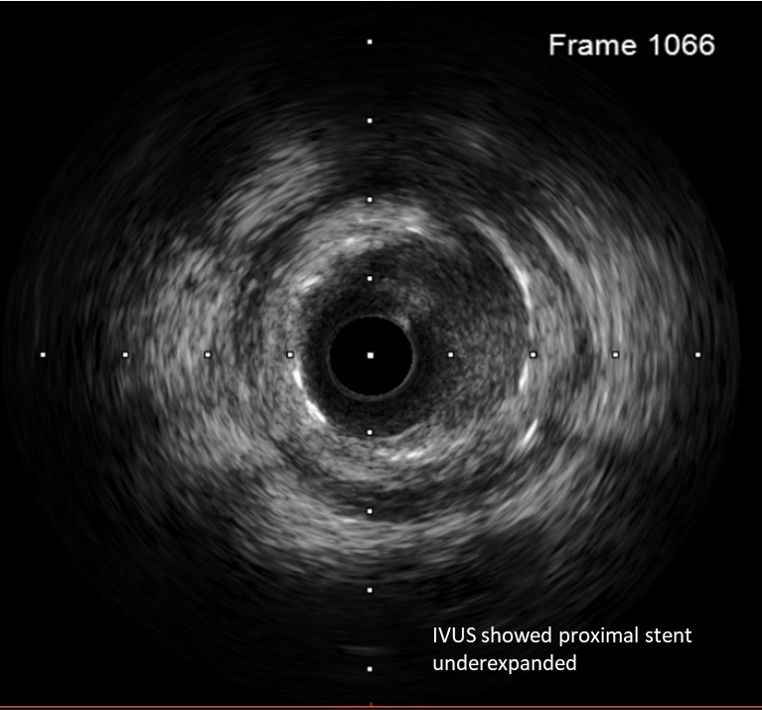

Percutaneous coronary intervention (PCI) was performed via transradial approach with 6 Fr radial sheath. Left coronary system was engaged using EBU 3.0 6 Fr guiding catheter. We decided for antegrade approach. Initial attempt with Fielder XT-A wire with a microcatheter support failed to cross the in-stent restenosis (ISR) lesion. We escalated to Asahi Gaia Second wire and successfully crossed the lesion to OM branch. Subsequently, wire was exchanged to a workhorse wire Runthrough Floppy via microcatheter. Lesion site was first predilated with a semi-compliant balloon Pantera Pro 2.0x 15 mm. Then, IVUS was passed down which showed previous stent site undersized, vessel size distal LCX of 4.0 mm. We further predilated lesion site with scoring balloon Scoreflex Trio 3.5x15 mm, up to 22 atm. Lesion site was acceptably prepared, then Paclitaxel drug-coated balloon Prevail 4.0x25 mm was deployed at nominal 6 atm for 60 seconds. Repeated IVUS run showed good stent apposition with MSA of 9.5mm2 proximally and 6.6mm2 distally. Final fluoroscopic shot showed good result with TIMI 3 flow, no stent edge dissection. Patient was symptom-free after procedure and discharged the following day.